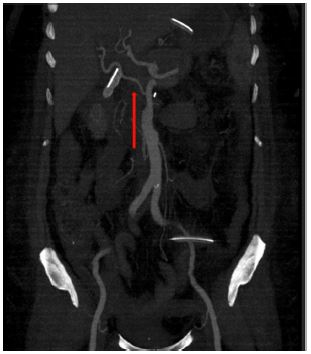

Nutcracker syndrome was another pathology found in this study which is the compression of the Left Renal Vein (LRV) between the aorta and (SMA). This condition is called “anterior nutcracker syndrome” (Figure 8). In contrast, a circumaortic or retro aortic LRV can also be compressed between the aorta and vertebral body, which is called the “posterior nutcracker syndrome”. One of the many causes of anterior nutcracker syndrome is aberrant SMA branching from the aorta. The patient may present as a case of pelvic congestion syndrome secondary to renal venous hypertension. The imaging findings are the presence of the beak sign (i.e., abrupt narrowing of the LRV between the aorta and SMA) with concomitant dilatation of the proximal LRV. Another CT parameter is a ratio of the LRV diameters at the hilar and aortomesenteric regions of more than 4.9. A few other findings include a reduced aortomesenteric angle (less than 41°) which is a very sensitive parameter /a measured beak angle of more than 32° [4].

Figure 8: Sagittal reformats of a patient with anterior nutcracker syndrome showing the compression of the left renal vein. (Blue arrow).